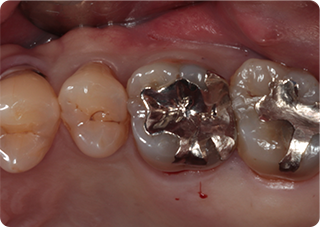

精密根管治療④

術前

術後

| 主訴 | 奥歯で噛むと痛い |

| 治療期間/回数 | 1ヵ月、3回 |

| 価格(税込) | 88,000円(税込) |

| リスク・副作用 | 病変再発、歯根破折の可能性 |

| ポイント | う蝕検知液を用い、むし歯の取り残しが無いようにし、ラバーダム防湿を行い、無菌的に根管治療を行った。根管充填材は、殺菌作用の強い保険適応外のMTAセメントを使用した。 |